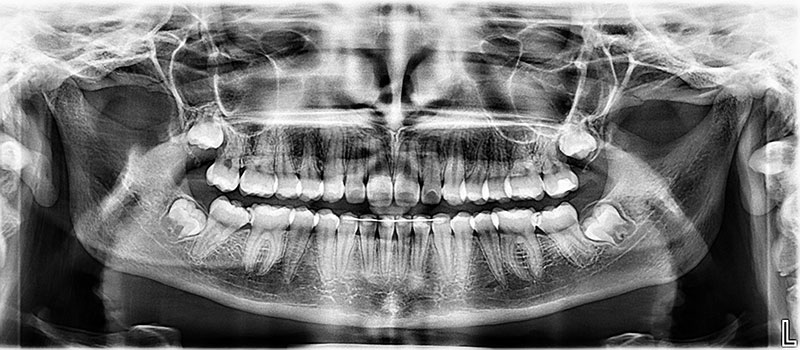

2 - Radiografía panorámica

En los pacientes menores de 20 años, incluidos los adolescentes y los niños, los dientes se desarrollan más rápidamente. Por tanto, el tipo de radiografía dental debe adaptarse a la edad del paciente:

- Una radiografía panorámica entre los 6 y los 8 años para comprobar que los dientes están completos;

- Una radiografía panorámica entre los 10 y los 13 años para asegurarse de que los dientes no están apiñados;

- Una radiografía panorámica entre los 18 y los 20 años para controlar el crecimiento de las muelas del juicio.